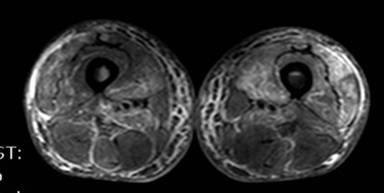

During the fourth cycle of chemotherapy, the patient reported persistent pain of both lower limbs causing major difficulties in mobilizing. The pain was described as crushing sensation and cramps localized to the anterior side of both thighs causing insomnia. Motor function, sensation and reflexes of lower limbs were normal. The skin had a paper-like texture in regard of the painful lesion. Biological markers were as follows: creatine kinase 1.6 N, lactate dehydrogenase 2.3 N and low levels of complement C3 and C4, with no evidence of inflammation. Doppler examination was unremarkable, hence excluding arterial or venous causes. MRI of lower limbs showed a diffuse T2 hyperintensity in both anterior muscles compartments associated with necrotic lesions (Figures 1 and 2), compatible with bilateral quadriceps polymyositis.

|

Figure 2. MRI (T2 SPAIR) axial section of both thighs. Necrotic areas (hyperintensity) of both vastus lateral quadriceps. |